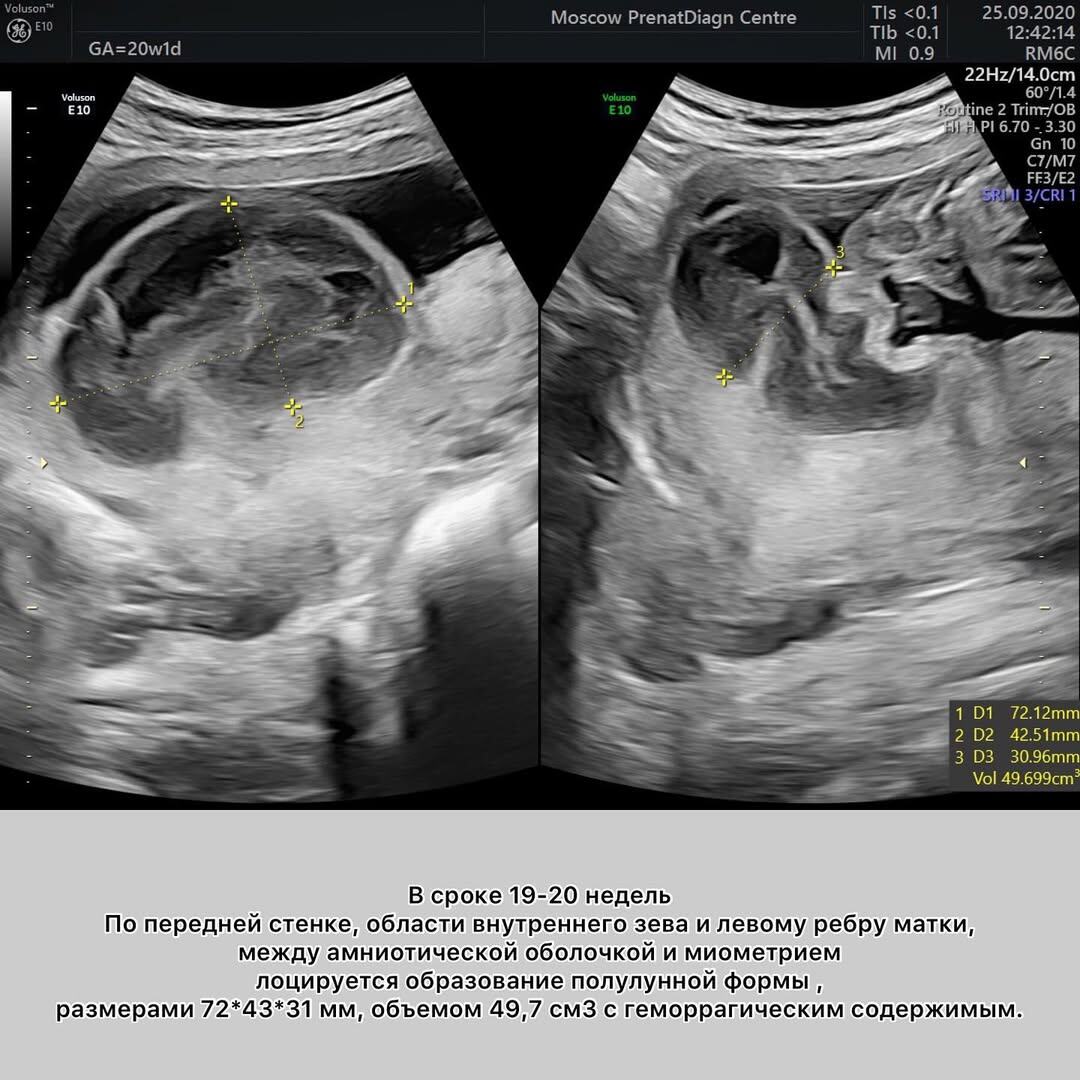

👉Смотрите в галерее, что произошло с ХАС в нашем случае.

Анины кровотечения продолжались до 25 недель. Хорошо, что ей хватило мужества не мчаться каждый раз в стационар на скорой, а ждать, зажав пальцы крестиком. В этой ситуации максимально возможный объем вмешательства — транексамовая кислота. Все остальное, включая постельный режим, не просто не приносит пользы, но даже вредит.

Надо прекратить искать «волшебную таблетку» и просто ждать, при каждом эпизоде кровотечения убеждаясь, что с ребенком все ок. Время должно было сработать на нас: по мере прогрессирования беременности полость постепенно «схлопывается» и кровотечения прекращаются. В случаях частичной ХАС прогноз благоприятный, даже при полной ХАС возможно благополучное завершение беременности.